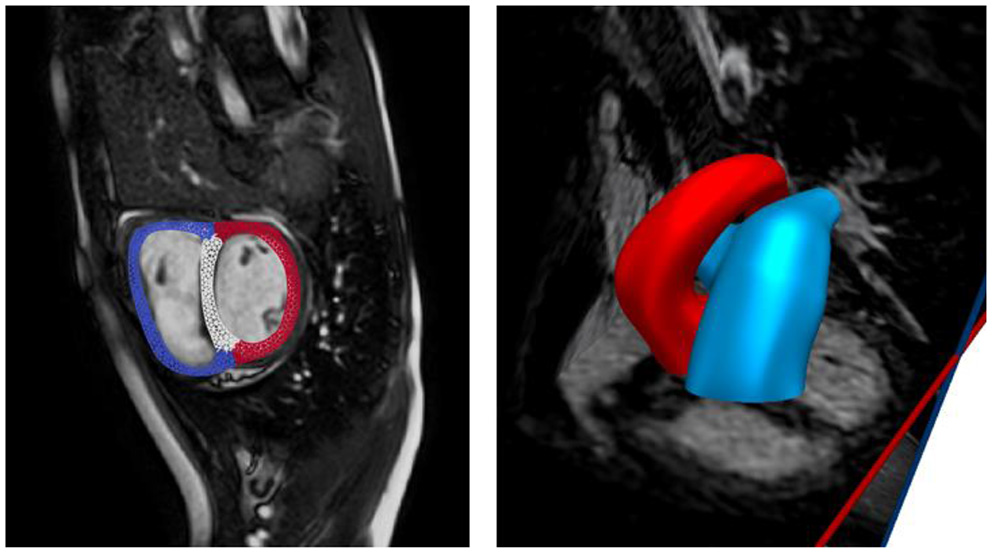

Biventricular and Vascular Geometries

Anatomical models of the LV, RV, aorta, and pulmonary arteries (PA) (consisting of the main, left, and right pulmonary arteries) were reconstructed from the acquired MR images. The biventricular model was reconstructed from images that correspond to the point in the cardiac cycle where ventricular pressures were lowest during filling (Geuzaine and Remacle, 2009). Furthermore, anatomical models of the aorta and large pulmonary arteries were reconstructed using the blood flow modeling software CRIMSON (www.crimson.software) (Figure 1).

FIGURE 1

www.frontiersin.org

Figure 1. Reconstruction of biventricular model (left) and large proximal arteries (right) from cine MR images.